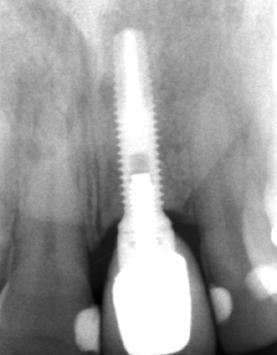

El lecho implantario se preparó mediante fresado biológico, ajustado al tipo de hueso y a las dimensiones del implante planificado. A continuación, se procedió a la inserción del implante, que alcanzó un torque de inserción adecuado, permitiendo dejarlo en fase de cicatrización con el pilar

correspondiente colocado. Una vez colocado el implante y el pilar de cicatrización, se realizó una técnica de sobrecorrección vestibular con el injerto particulado inmerso en PRGF-Endoret, recubriendo toda la zona con una membrana autóloga de fibrina (fracción 1 activada y retraída). Se suturó con monofilamento no reabsorbible, sin tensión, para evitar el colapso del volumen vestibular que se buscaba ganar (Figuras 7 a 10). Como provisional se empleó el propio diente de la paciente, ferulizado a los adyacentes con resina, a modo de puente Maryland (Figura 11).

Tras 6 meses de oseointegración, se procedió a la confección de la prótesis definitiva. En aquel momento, hace 22 años, se eligió un biopilar microfresado y una corona metal-cerámica cementada, que representaban la mejor alternativa para garantizar un sellado adecuado y una estética satisfactoria en el sector anterior. En la actualidad, la opción preferible habría sido una prótesis atornillada con un elemento intermedio (transepitelial unitario) y una corona totalmente cerámica cementada a una interfase. No obstante, es importante contextualizar la decisión en función de la época en la que se finalizó el caso (Figuras 12 y 13).

un cone beam de control para valorar el estado de un tratamiento endodóntico en la pieza 26; en el corte seccional correspondiente al implante se aprecia una estabilidad completa, con un volumen vestibular óseo significativo.

Estos hallazgos confirman el éxito del procedimiento quirúrgico y de la posterior carga progresiva, con un mantenimiento óptimo de los tejidos duros y blandos a lo largo de más de dos décadas (Figura 15). Los cambios entre el momento inicial y el final del tratamiento son evidentes, especialmente al comparar la imagen intraoral de la primera visita con la tomada a los 22 años, donde la mucosa que rodea al diente 21 —y posteriormente al implante— se muestra engrosada, en buen estado de salud y con una estética destacable. Asimismo, la comparación entre la radiografía inicial, que evidenciaba el fracaso del tratamiento de conductos del diente en posición 21, y la radiografía a los 22 años, que muestra el implante sin pérdidas óseas asociadas, resulta elocuente (Figuras 16 a 19).

Figura 13. Radiografía final con la prótesis recién colocada.

una estabilidad completa del tejido óseo circundante.

En el caso presentado, el itinerario biológico —exodoncia, regeneración del alveolo con PRGF-Endoret, inserción temprana con fresado biológico, sobrecorrección vestibular mediante injerto autólogo particulado embebido en PRGF y cobertura con membrana autóloga de fibrina— se alinea con la tendencia actual hacia procedimientos mínimamente invasivos y autólogos

Figura 15. Corte seccional del implante en posición 21, donde se observa